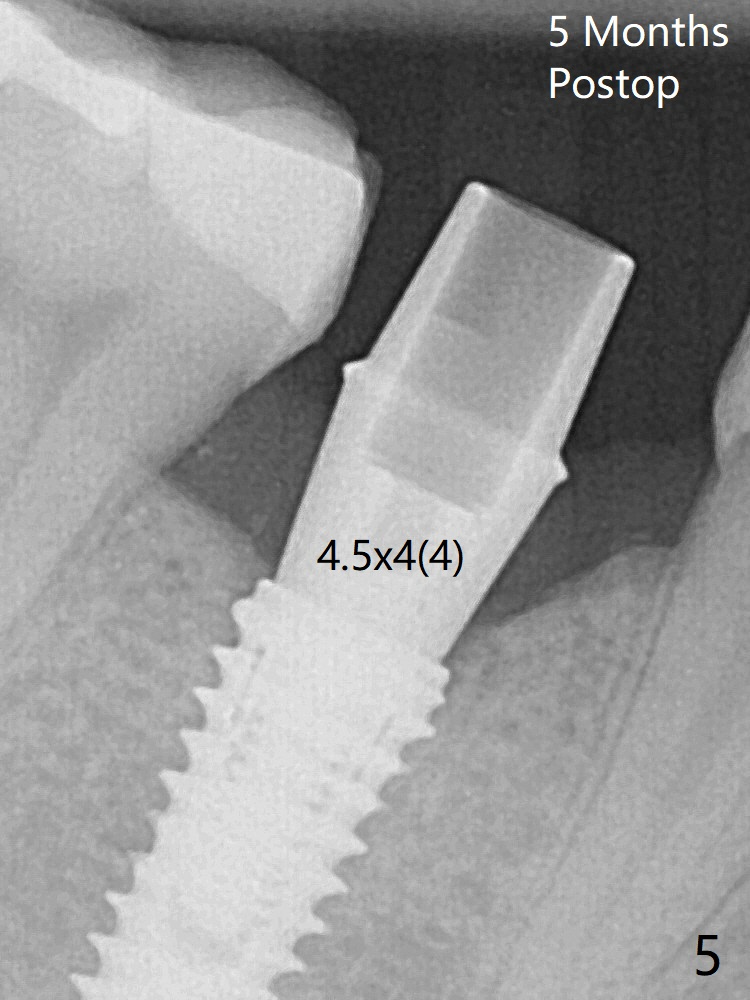

Osteotomy starts in the lingual slope of the socket of #29 with Point/Lindamann bur, but a little too distal. Gradually the osteotomy is moved mesial; the trajectory and position (Fig.1) are better than designed, but the osteotomy is close to the Mental Loop (red dashed line). When a 4x11.5 mm implant is placed, it appears to overlap the buccally positioned Loop (Fig.2 red dashed line). In fact there is no postop paresthesia. The implant placement level seems to be ideal (Fig.3 after bone graft). There is foul smell from the immediate provisional; in fact it may be due to the loose contact between the implant and abutment (Fig.4 < (4 months postop)). The gingiva is unhealthy. A 5.5x5 mm healing abutment is placed. When the patient returns 5 months postop, the gingiva is healthy after removal of the healing abutment. A 4.5x4(4) mm cemented abutment is seated without interference and torqued to 35 Ncm (Fig.5).